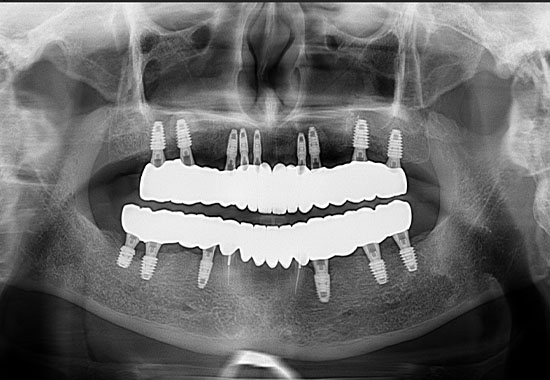

BEFORE

AFTER

- 식립 개수 : 17개 (상악 9개 하악 8개)

- 수술 내용 : 상악동거상술, 치조골 이식